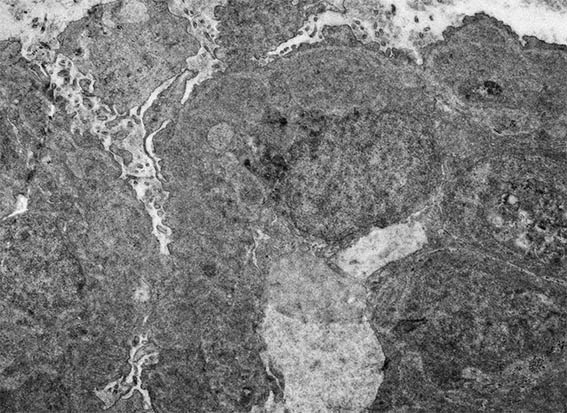

Figure 11. Electron microscopy, original magnification, X4,000. Note extensive podocyte damage, severe thickening of capillary walls, endothelial cell enlargement, and electron-dense subendothelial areas.